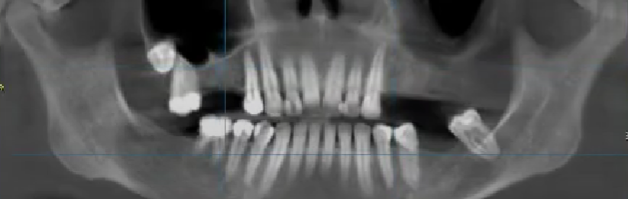

У Екатерины не хватало нескольких зубов. На верхней челюсти отсутствовали зубы 1.5, 1.6, 2.4, 2.5, 2.6, 2.7, на нижней — 3.5, 3.6 и 4.7👇

На первом приеме мы провели Екатерине осмотр и консультацию, сделали КТ и ортопантомограмму (ОПТГ) — панорамный рентгеновский снимок зубов на обеих челюстях.

Однако в случае Екатерины, как это ни удивительно, синус-лифтинг не потребовался: у пациентки осталось много костной ткани по вертикали, туда вполне можно поместить средние имплантаты 8-10 мм.